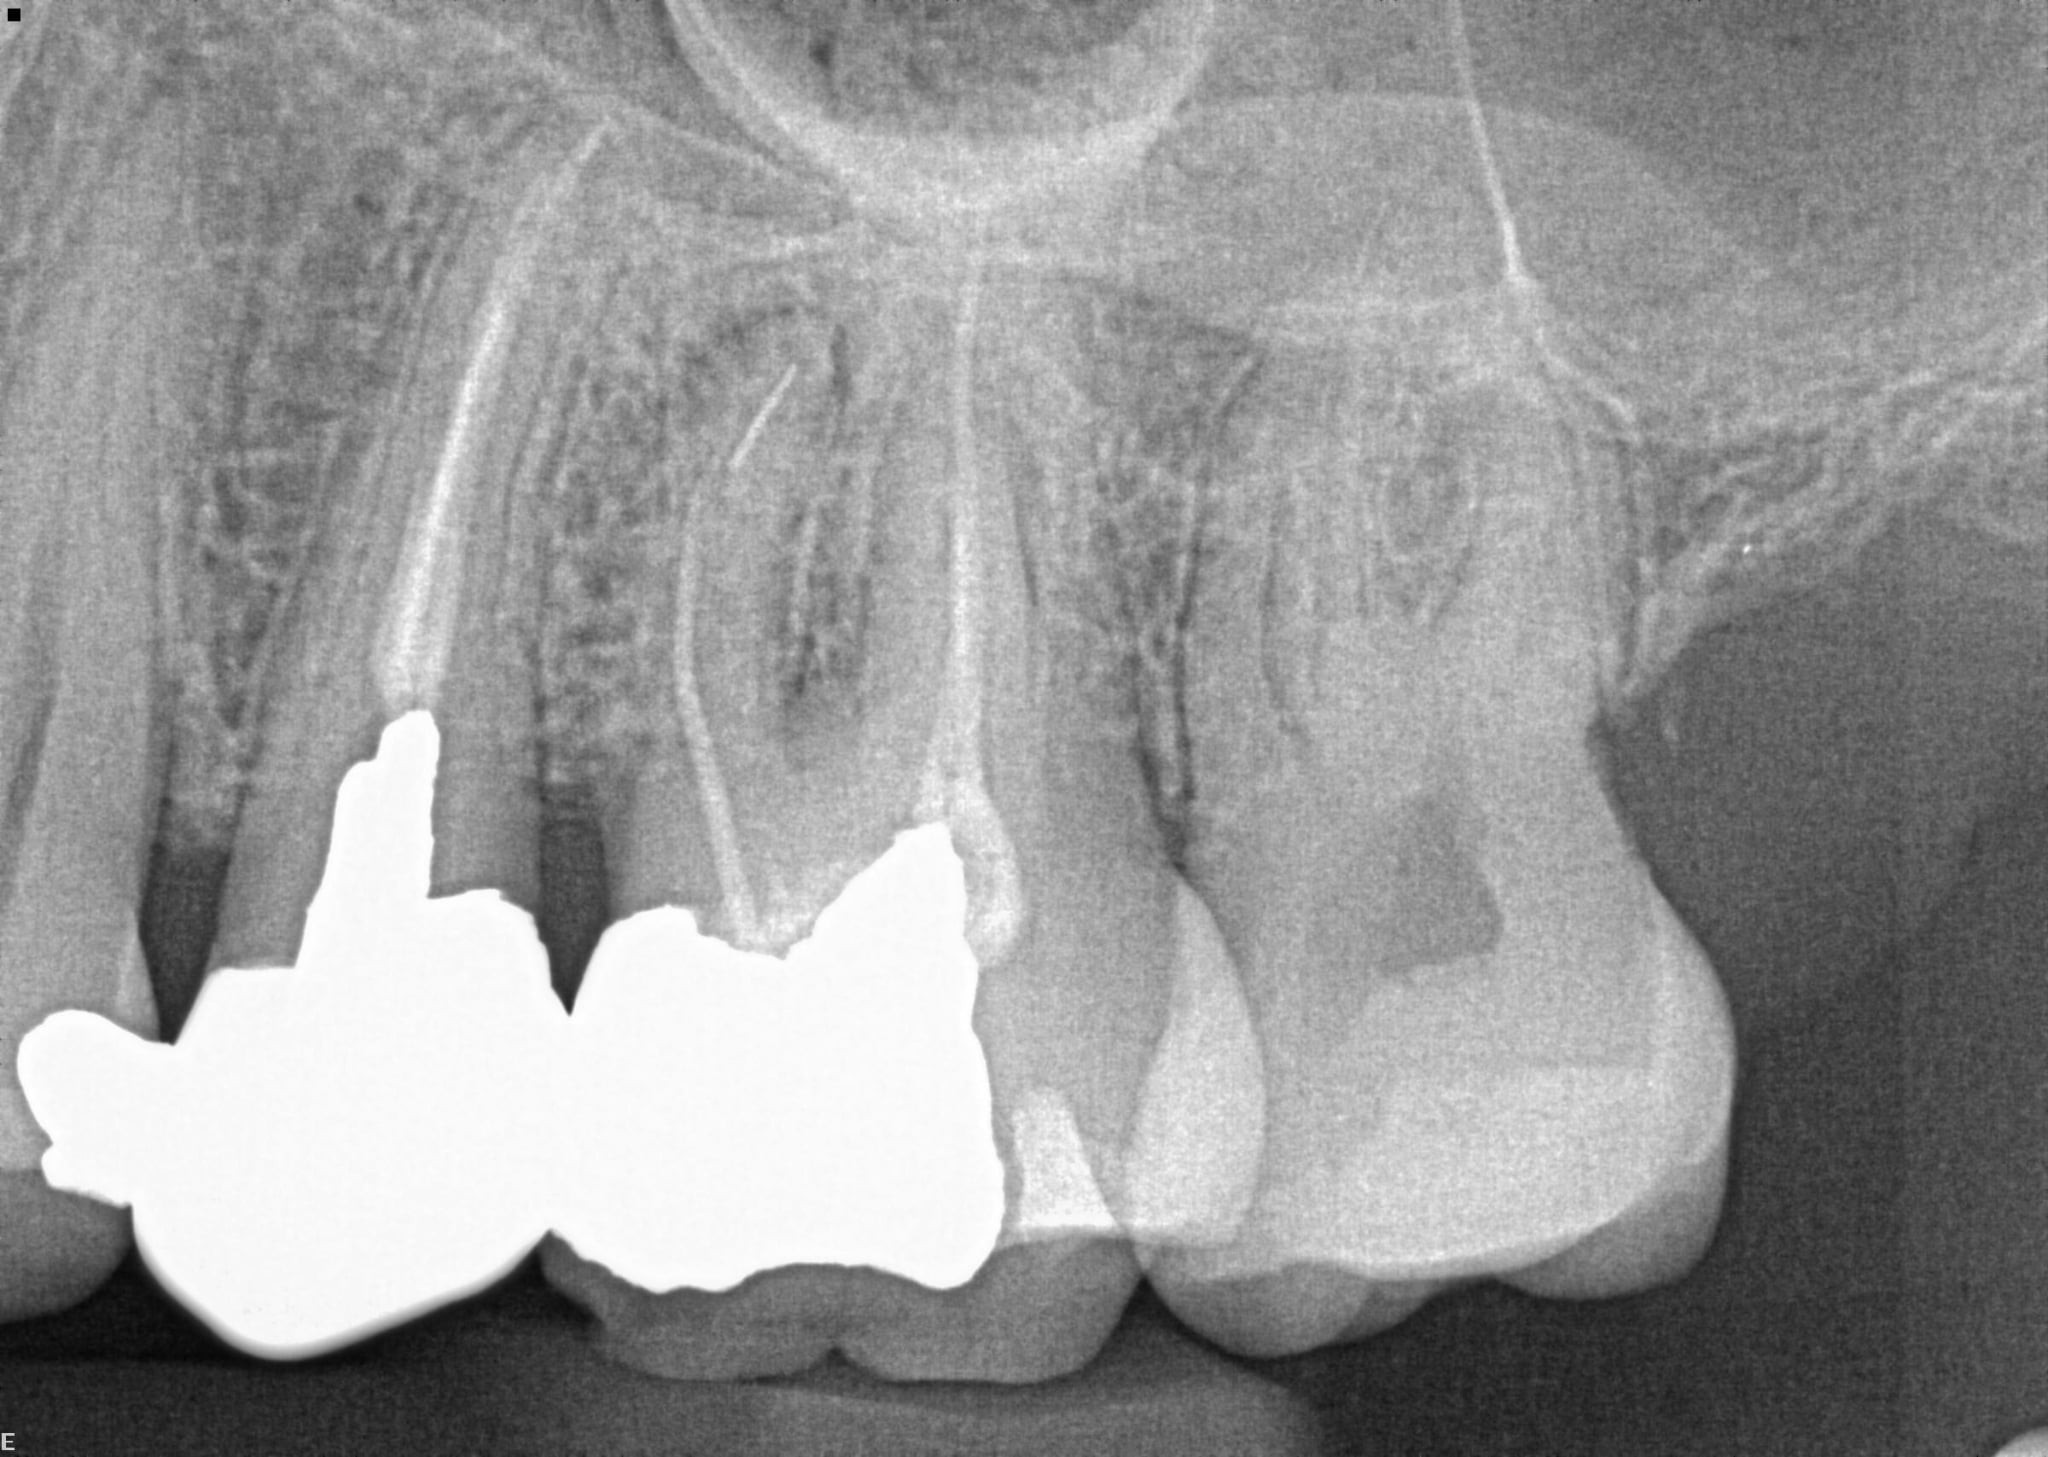

2. What option can describe the post placement in the X ray bellow for the tooth # 4.6?